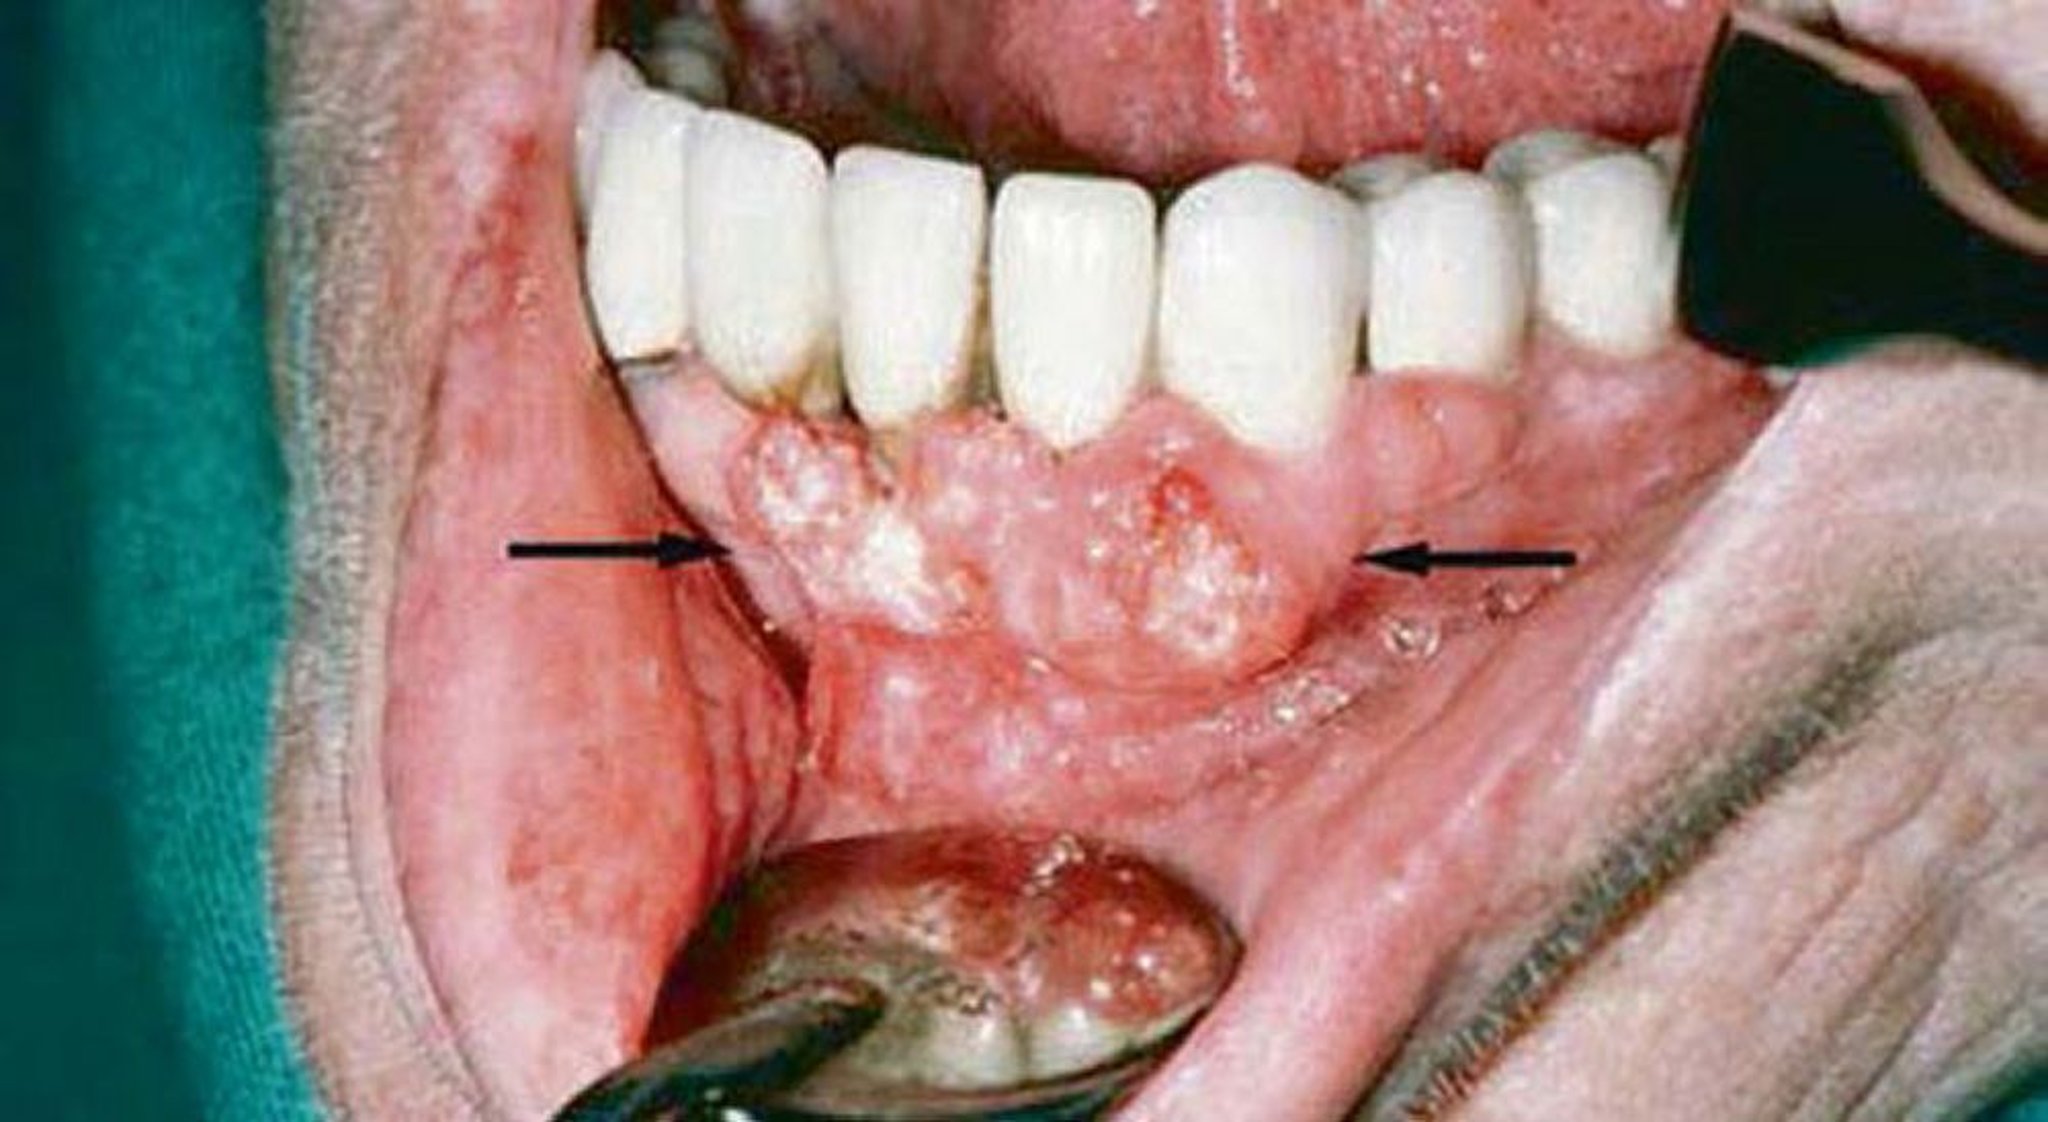

Carcinoma epidermoide (lesiones gingivales)

El examen gingival de este paciente mostró evidencias de carcinoma epidermoide. Los estudios de diagnóstico por imágenes mostraron la invasión de la mandíbula.